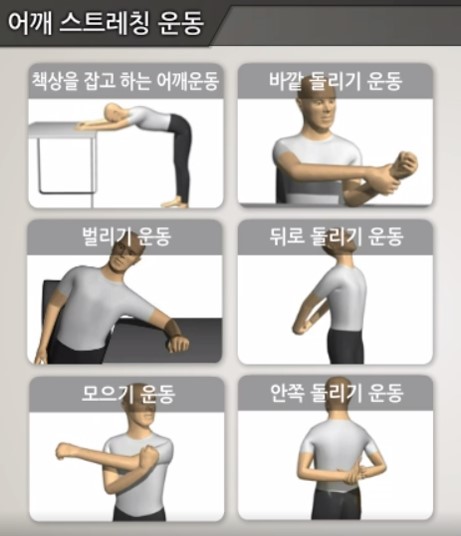

석회성건염의 치료의 목표는 석회를 제거하는 것이 아니라, 증상을 호전시키는 것이다. 우선적으로 스트레칭 등의 물리치료, 약물치료 등의 보존적인 치료를 시행하게 되며, 대부분 보존적 치료에 잘 반응하게 된다. 하지만 통증이 극심하고, 보존적 치료에 효과가 없을 시에는 스테로이드 주사 치료 및 체외충격파 시술 등을 시행해 볼 수 있으며, 비수술적 치료에도 반응하지 않을 때는 관절경을 이용한 수술적 치료도 시행해 볼 수 있다.

대개 보존적 치료에 반응을 잘하는 편이나, 통증으로 인한 유착성 관절낭염이 발생하게 되면, 유착성 관절낭염으로 인한 증상을 지속적으로 호소할 수 있다. 이에 꾸준한 스트레칭 운동을 통하여 관절 가동범위를 유지시키는 것이 중요하다.

평소에 운동 전 예비 운동 및 스트레칭을 통하여 어깨 관절의 가동범위를 유지하는 것이 중요하다.